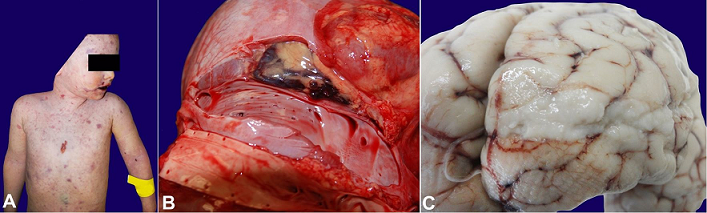

When WFS is full-blown, it can be detected macroscopically at the external examination thanks to characteristic signs, such as cutaneous petechiae ( Figure 1A), and at internal dissection due to purulent meningeal and cerebral matter and adrenal gland hemorrhage —small bleedings usually located at the cortical-medullary junction that can be detected with a careful histological examination. 6 The sampling of these cadavers requests a befitting selection of the biological fluids that must be collected with sterile syringes and stored in sealed vials: cardiac blood 9,13 and cerebrospinal fluid 3,14 are the most fitting samples; moreover, the examiner can proceed with the sampling of cadaveric parenchyma with sterile lancet and clamps, and storage in sealed vials. It is also advisable to sample the spleen, 9,14 heart, and liver. 15 In addition, an extensive cerebral sampling is recommended, including: leptomeninges, 3 cerebral hemispheres’ base and convexity (frontal, temporal, parietal, and occipital lobes), cerebellum (hemispheres and vermis), brainstem (midbrain, pons, and medulla oblongata), and spinal cord (cervical, thoracic, abdominal, and sacrum-coccygeal). The CDC guidelines 12 recommend to start a post-exposure antimicrobial chemoprophylaxis within 24 hours.

This study was conducted at the Legal Medicine Section of the University of Milan. We selected five patients (three males and two females aged between 2 months and 23 years) who suddenly died after showing symptoms of persistent fever. The autopsy was performed on all five patients between 48 hours and 10 days after death. Three cases (2, 3, 4) had adrenal apoplexy ( Figure 1B) and meningitis signs ( Figure 1C). Two cases (1, 5) did not show signs of meningitis.